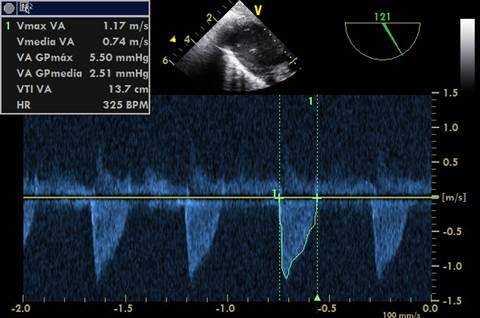

IVT: En plano transgástrico profundo alineando la señal doppler pulsado al TSVI. Imagen 3

IVT: Se remarcaba el contorno del espectro doppler pulsado del TSVI.